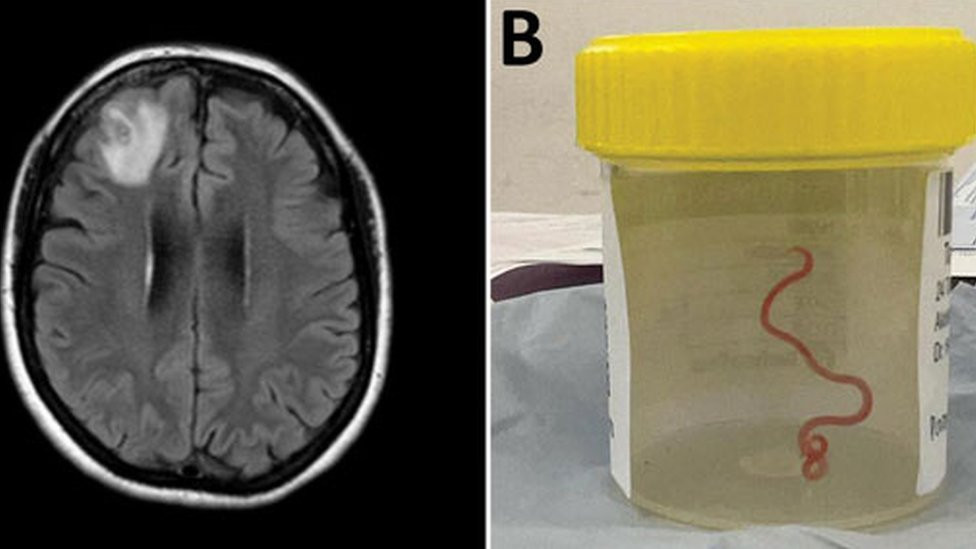

Australija i medicina: Lekari pronašli živog crva u mozgu žene tokom operacije

BBC | 29.08.2023.